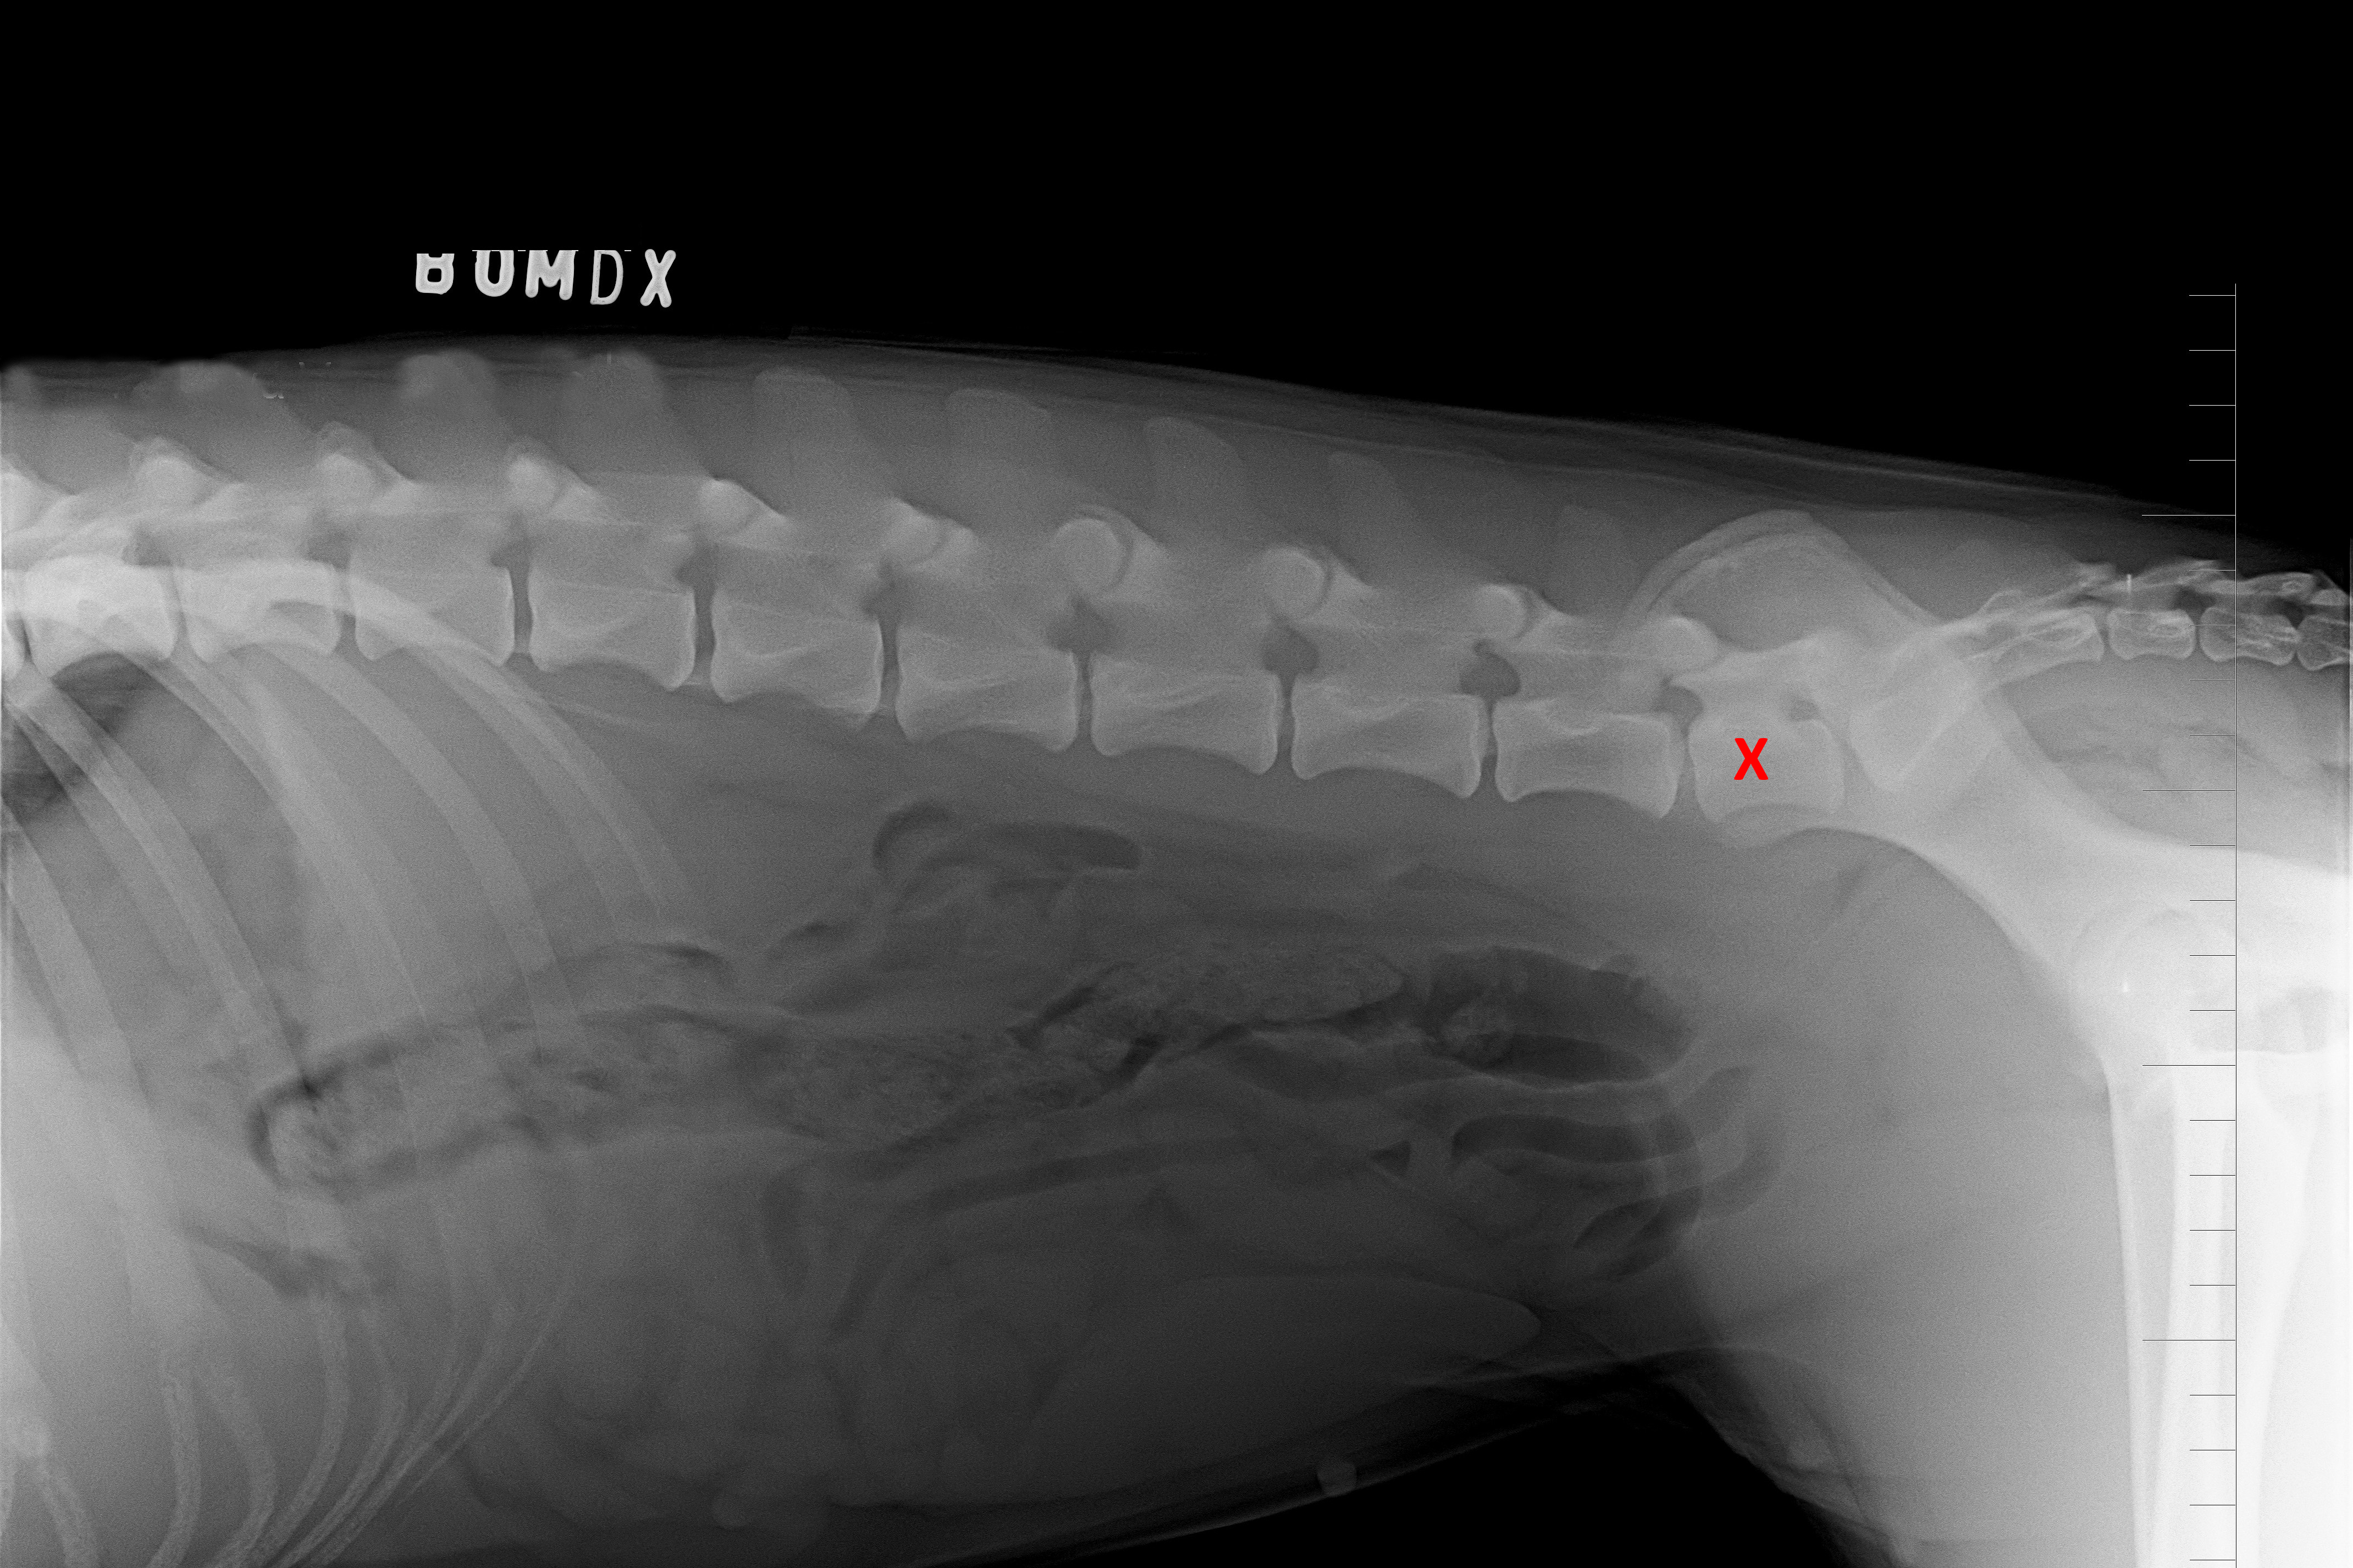

(1) 7 týdnů VD

(1) typ 3

(2) 7 týdnů lat

(2) typ 3 I